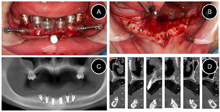

术前拍摄CBCT、口外、口内临床照片,进行种植位点分析与牙槽骨测量,从CBCT图像可见余留牙牙根形态完整,缺牙区域牙槽嵴严重萎缩,骨高度和骨宽度均不足,骨质未见明显异常,且下颌神经前环以及和下颌切牙管位置表浅,常规种植位点无法支持种植固定义齿修复(图9)。

将CBCT的DICOM数据转为STL格式后获得数据模型,找到下颌切牙管前端A,颏孔C,和A与C曲线的中点B,在A点和B点设置两颗固位钉,联合颏孔C形成下颌切牙管指示定位导板(图11,图12,图13,图14,图15)。

牙槽嵴顶切开翻瓣,找到颏孔位置,安放下颌管指示导板。在下颌管指示导板的引导下,去除下颌神经管颊侧骨壁,充分暴露下颌管神经前端和中段,用上颌窦外提升器械将下颌管神经向远中轻推,观察到剥离后下颌管神经向远中回缩(图16)。

安放骨支持式种植导板,在导板引导下用先锋钻在牙槽窝定点和定方向,种植窝直径2.4~2.8mm后停止扩孔,植入Nobel Active 3.5mm×8mm种植体,利用种植体的自攻性到达预定深度,均在骨平面以下,6颗种植体尽量保持在一个平面利于后期修复,所有种植体初期扭矩达到50N/cm,然后平整骨面,安放复合基台(图17)。